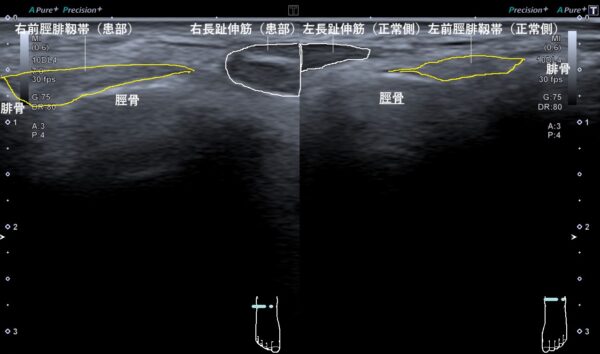

そこで、超音波(エコー)画像観察を行ってみると、右前脛腓靱帯(すねとくるぶしの骨をつないでいる靱帯)と長趾伸筋(足の人差し指から小指を伸ばす筋肉)が損傷して腫れていました(画像、白線と黄色線で囲んだ大きさの比較)。

これは、右足首を内側に捻った際に、靱帯と筋肉が強い力で引き伸ばされたことで、それぞれの組織に微細な断裂が起こり腫れてしまったと考えられました。